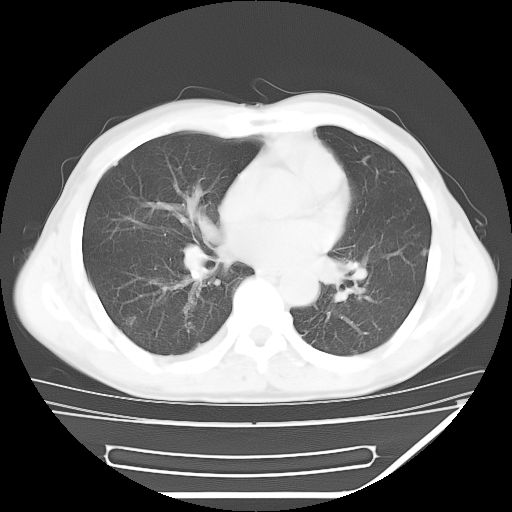

男,59岁,“结核性胸膜炎”30余年,胸部经常疼痛,多次x检查提示“肺部”炎症。腹部疼痛5日,b超提示:“肝内短管结石,余显示不清,建议进一步检查。”

两肺结核并右侧胸腔积液;脾脏、腹腔及腹膜后淋巴结结核[陈旧性];肝内胆管结石

胸部腹部都是结核(双肺。纵隔淋巴结,肝脏,脾脏,肠系膜)

两肺结核并右侧胸腔积液;脾脏、腹腔及腹膜后淋巴结结核[陈旧性];肝内胆管结石。直肠息肉?